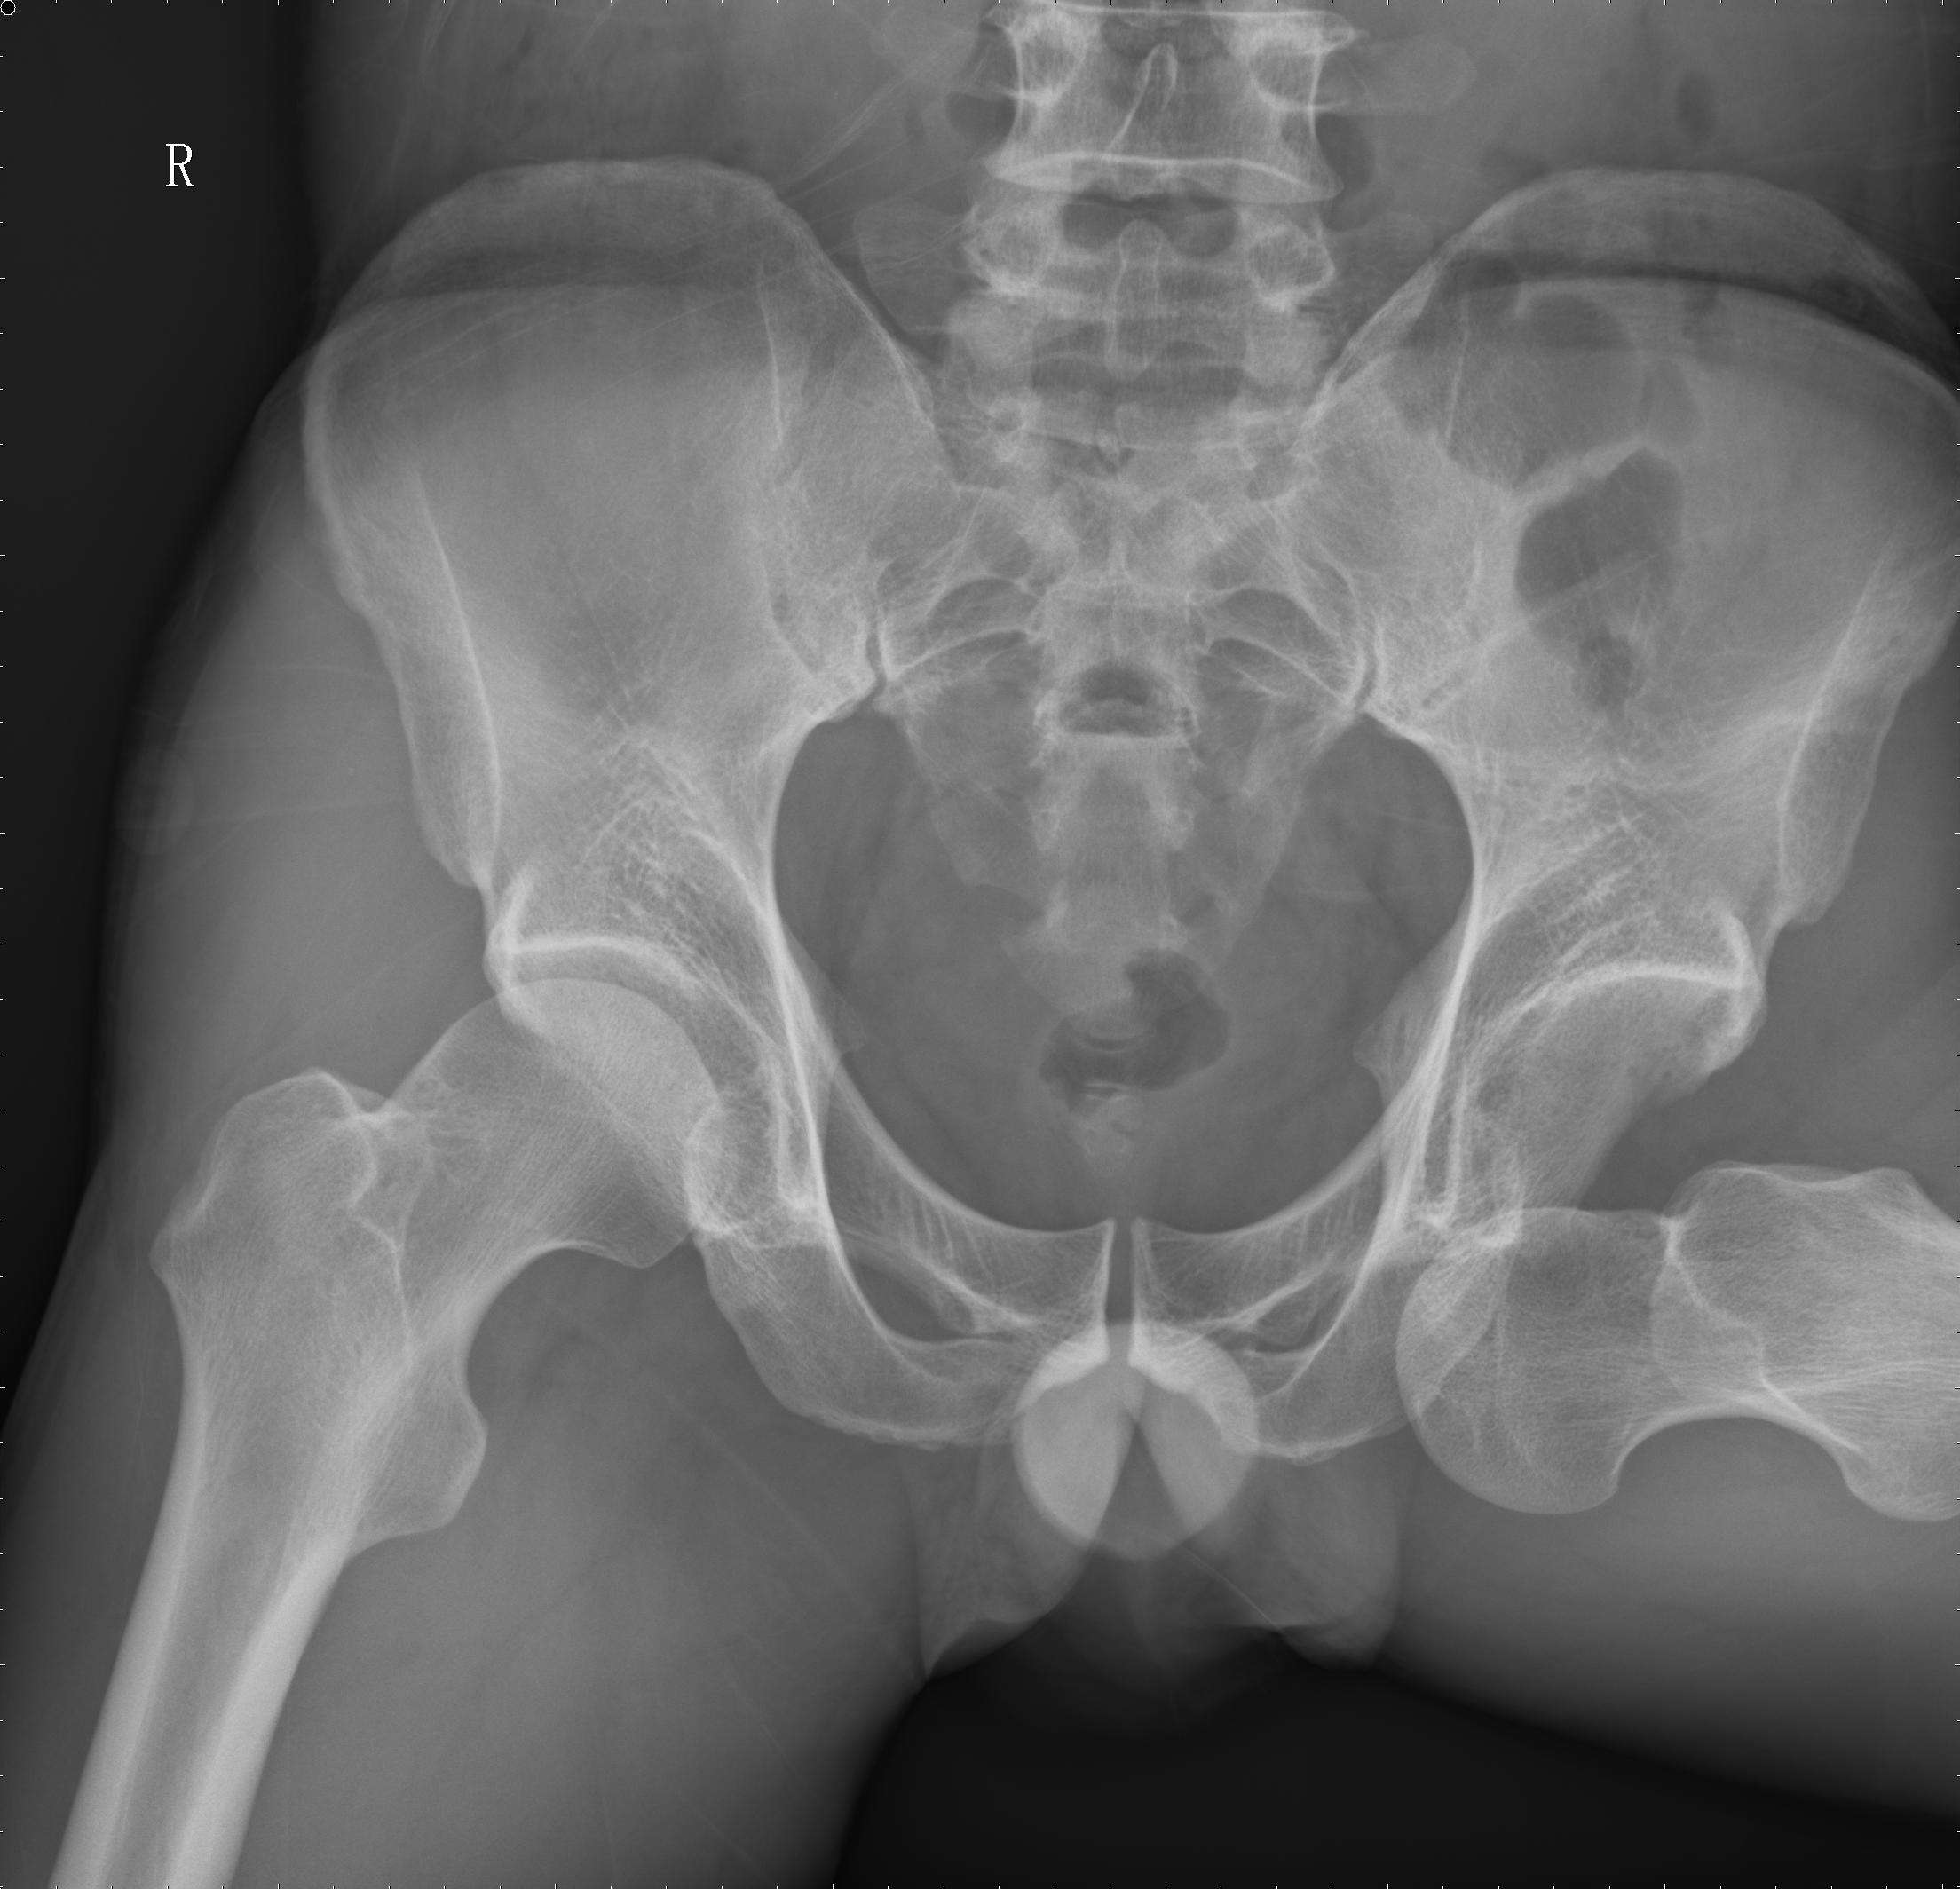

髖關節X光照片(資料圖)

家住武昌的楊太婆今年103歲,30年來她一點葷腥都不沾。上週六晚,她洗完澡剛走出衞生間,腳一滑重重摔倒在地。家人把她扶起來,聽到她直喊胯骨疼,完全無法挪步,家人趕緊就近把她送到武漢大學人民醫院。檢查顯示:嚴重骨質疏鬆,右側髖關節骨折,當即被收入骨科。